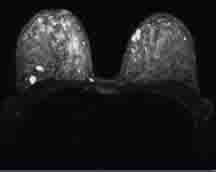

Figure 1 Dense, fibrocystic breast with no well-defined abnormality.

Eight days later at a follow-up MRI, day 17 of her menstrual cycle, she had multiple breast cysts (Fig.1) and florid, extensive bilateral background enhancement (fig. 2). She also had prominent right axillary nodes(Fig.3). The results showed there was no definite malignant disease. (BIRADS 2)